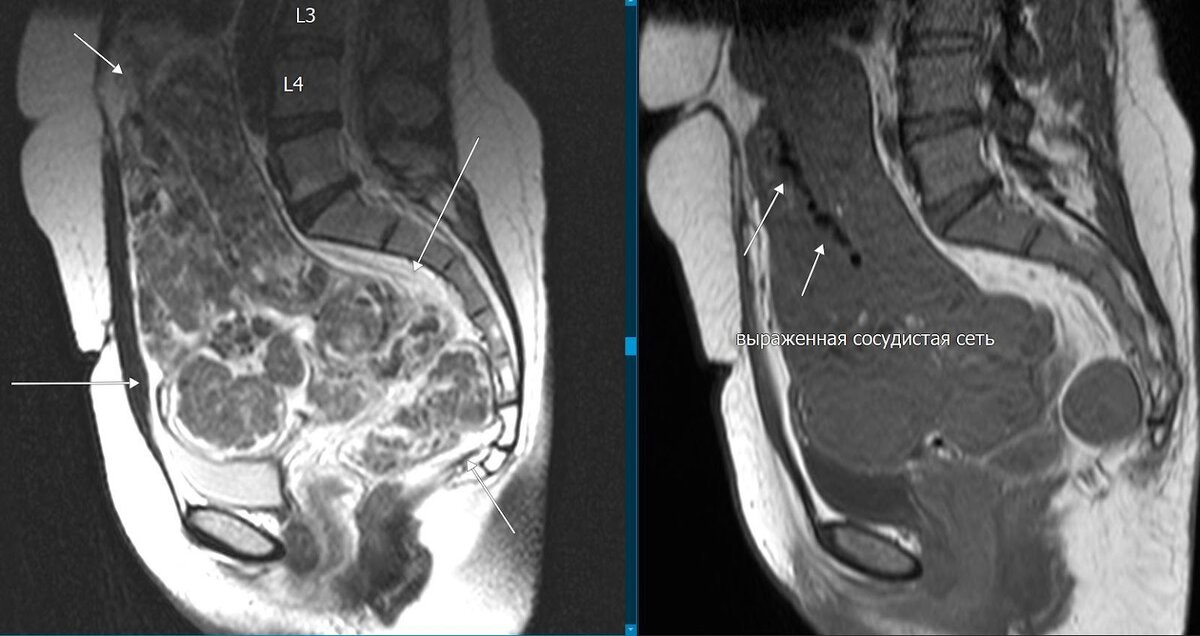

Рис.1. ΠžΠ±Ρ€Π°Π·ΠΎΠ²Π°Π½ΠΈΠ΅, Π·Π°Π½ΠΈΠΌΠ°ΡŽΡ‰Π΅Π΅ всю ΠΏΠΎΠ»ΠΎΡΡ‚ΡŒ ΠΌΠ°Π»ΠΎΠ³ΠΎ Ρ‚Π°Π·Π°, Π½Π°Π»ΠΈΡ‡ΠΈΠ΅ сосудистой сСти.

ΠœΠ°Ρ‚ΠΊΠ° ΡƒΠ²Π΅Π»ΠΈΡ‡Π΅Π½Π° Π² Ρ€Π°Π·ΠΌΠ΅Ρ€Π°Ρ…, растянута Π΄ΠΎ уровня Ρ‚Π΅Π»Π° L4 ΠΏΠΎΠ·Π²ΠΎΠ½ΠΊΠ°, ΠΎΡ‚ΠΊΠ»ΠΎΠ½Π΅Π½Π° Π²ΠΏΡ€Π°Π²ΠΎ, ΠΌΠΈΠΎΠΌΠ΅Ρ‚Ρ€ΠΈΠΉ прСдставлСн Π² Π²ΠΈΠ΄Π΅ ΠΌΠ½ΠΎΠ³ΠΎΡƒΠ·Π»ΠΎΠ²Ρ‹Ρ… ΠΎΠ±ΡŠΠ΅ΠΌΠ½Ρ‹Ρ… ΠΎΠ±Ρ€Π°Π·ΠΎΠ²Π°Π½ΠΈΠΉ (3,4,5,6,7Β  ΠΏΠΎ FIGO), Π·Π°Π½ΠΈΠΌΠ°ΡŽΡ‰ΠΈΡ… всё пространство ΠΌΠ°Π»ΠΎΠ³ΠΎ Ρ‚Π°Π·Π°, с распространСниСм Π½Π° Π½ΠΈΠΆΠ½ΠΈΠΉ этаТ Π±Ρ€ΡŽΡˆΠ½ΠΎΠΉ полости. ΠžΠ±Ρ‰ΠΈΠ΅ Ρ€Π°Π·ΠΌΠ΅Ρ€Ρ‹ патологичСской Π·ΠΎΠ½Ρ‹ 19,5*16,2*22,4 см (Ρ„Ρ€ΠΎΠ½Ρ‚*саг*Π²Π΅Ρ€Ρ‚). ΠžΠ±Ρ€Π°Π·ΠΎΠ²Π°Π½ΠΈΡ с Ρ‡Π΅Ρ‚ΠΊΠΈΠΌΠΈ Ρ€ΠΎΠ²Π½Ρ‹ΠΌΠΈ ΠΊΠΎΠ½Ρ‚ΡƒΡ€Π°ΠΌΠΈ, Π½Π΅ΠΎΠ΄Π½ΠΎΡ€ΠΎΠ΄Π½ΠΎΠΉ структуры с Π½Π°Π»ΠΈΡ‡ΠΈΠ΅ΠΌ Π²Ρ‹Ρ€Π°ΠΆΠ΅Π½Π½ΠΎΠΉ сосудистой сСти, Π΄ΠΈΠ°ΠΌΠ΅Ρ‚Ρ€ΠΎΠΌ Π΄ΠΎ 0,5 см. ΠžΠ±Ρ€Π°Π·ΠΎΠ²Π°Π½ΠΈΠ΅ оттСсняСт ΠΈ смСщаСт ΠΏΠ΅Ρ‚Π»ΠΈ ΠΊΠΈΡˆΠ΅Ρ‡Π½ΠΈΠΊΠ° ΠΊΡ€Π°Π½ΠΈΠ°Π»ΡŒΠ½ΠΎ, имССтся масс-эффСкт Π½Π° ΠΌΠΎΡ‡Π΅Π²ΠΎΠΉ ΠΏΡƒΠ·Ρ‹Ρ€ΡŒ.

ΠŸΡ€ΠΈ Π²/Π² контрастном динамичСском усилСнии Π²Ρ‹ΡˆΠ΅ΠΎΠΏΠΈΡΠ°Π½Π½Ρ‹Π΅ структуры постСпСнно Π½Π°ΠΊΠ°ΠΏΠ»ΠΈΠ²Π°ΡŽΡ‚ контраст,Β  с Π½Π΅ΠΎΠ΄Π½ΠΎΡ€ΠΎΠ΄Π½Ρ‹ΠΌ Π½Π°ΠΊΠΎΠΏΠ»Π΅Π½ΠΈΠ΅ΠΌ Π½Π° постконтрастных Ρ‚ΠΎΠΌΠΎΠ³Ρ€Π°ΠΌΠΌΠ°Ρ….